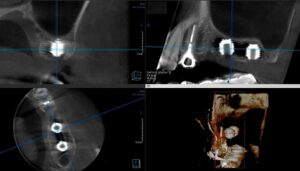

• 症例2014-013

ショートインプラント症例

今日のインプラントの症例は、ちょっと面白い症例です。 左の上の歯が3本なくて、しかも骨の高さが足りませんでした。そこで、造骨する事無く後ろ側に二本のショートインプラントをいれました。 そんな、症例のCT画像です。 インプラントにもただ、白い […] 本文を読む